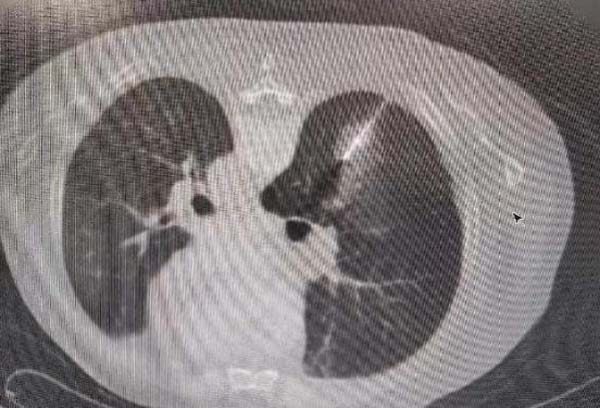

消融治疗中:

一种具有创伤小、疗效明确、安全性高、可重复性强、适应人群广等特点的局部热消融术——微波消融(MWA),作为一种精准的微创治疗方式进入了肺结节的治疗视野中。

微波消融(MWA)一般采用915 MHz或2,450 MHz两种频率。在微波电磁场的作用下,肿瘤组织内的水分子、蛋白质分子等极性分子产生极高速振动,造成分子之间的相互碰撞、相互摩擦,在短时间内产生高达60℃-150℃的高温,从而导致细胞凝固性坏死。由于辐射器将微波能集中在一定范围内,故而能有效地辐射到所需靶区。微波消融只会损伤局部设定范围内的细胞而不会破坏周围的组织,消融范围可控。

因此,本次手术方案中一次穿刺操作,既可以取得结节的病理结果,又可以消融结节,使患者在最小的创伤下得到最大的获益。